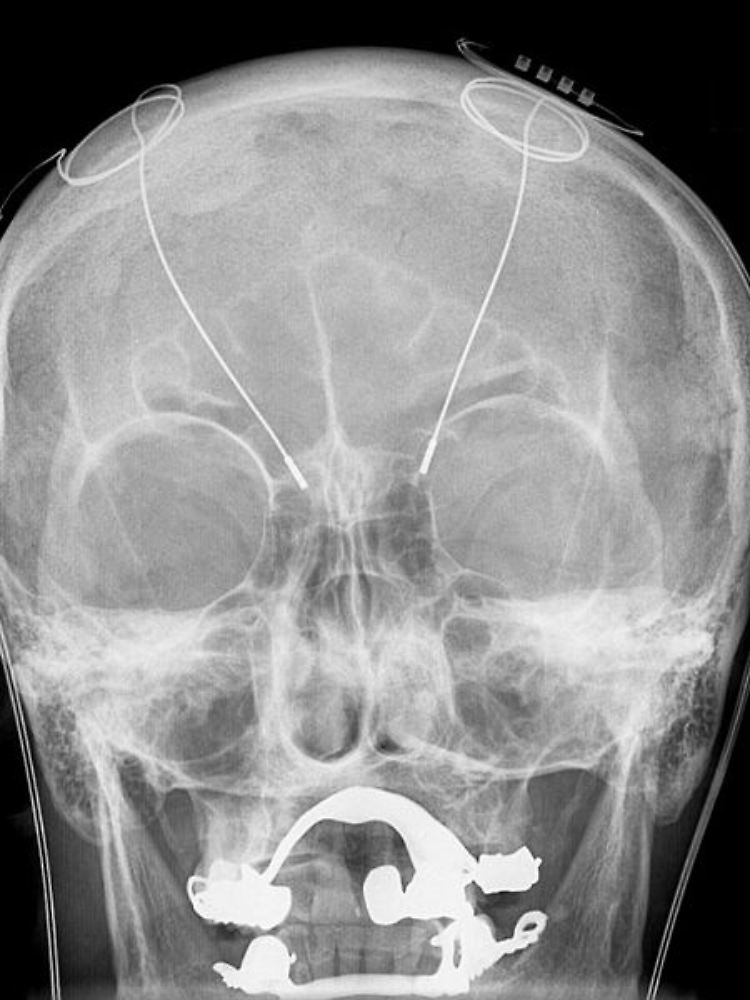

Keine Frage, es gibt sie bereits: Menschen mit einem Hirnimplantat. Und es sind nicht einmal wenige. Schon mehr als 80.000 Männer und Frauen auf dieser Welt haben sich eine Elektrode ins Hirn pflanzen lassen. Auch in Deutschland sind diverse Kliniken auf diesen Eingriff spezialisiert. In Kiel, Köln, Berlin und fast 30 anderen Orten der Republik stecken Neurochirurgen bei insgesamt rund 400 Patienten im Jahr Metallnadeln durch kleine Löcher in der Schädeldecke weit in den Kopf hinein. Ihr Ziel: die Tiefe Hirnstimulation.

"Die elektrischen Sonden werden genau in die Hirnregion eingesetzt, in der die Funktion der Nervenzellen gestört ist", erklärt Günther Deuschl, Direktor der Klinik für Neurologie in Kiel und Präsident der Internationalen Gesellschaft für Bewegungsstörungen. Über ein subkutan verlegtes Kabel sind die Elektroden mit einem Schrittmacher verbunden, der meist unterhalb des Schlüsselbeins sitzt. "Durch schwache Stromstöße", erläutert Deuschl, "wird dann eine permanente elektrische Reizung der Hirnregion verursacht, die gezielt überaktive Nervenzellen hemmt."